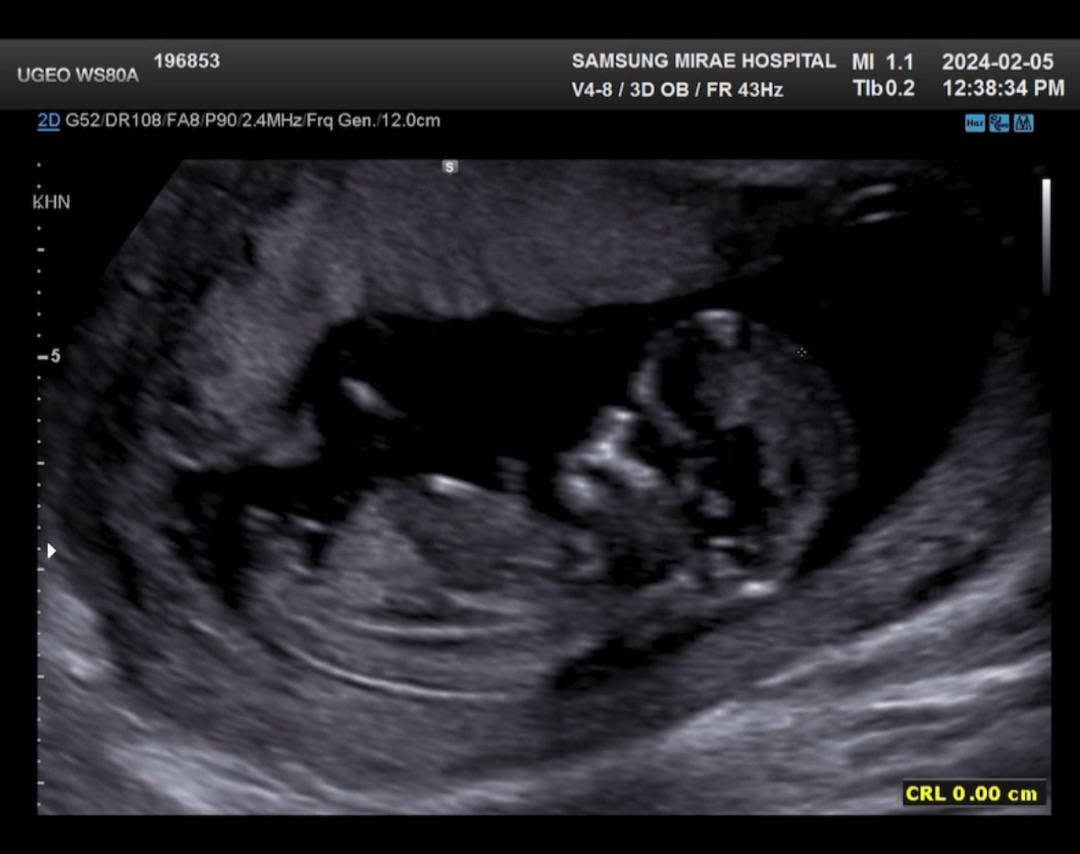

12주차 각도법 고수님들 부탁드려요!!

12주차 진입해서 병원에서 초음파보고왔습니다! 애기가 잘 안움직여줘서 옆모습 사진이 이것밖에 없네요ㅠㅠ 잘 안보이시겠지만 이 사진으로도 알수있을까요??

잘 안보이긴 하는데 아들인거같아용